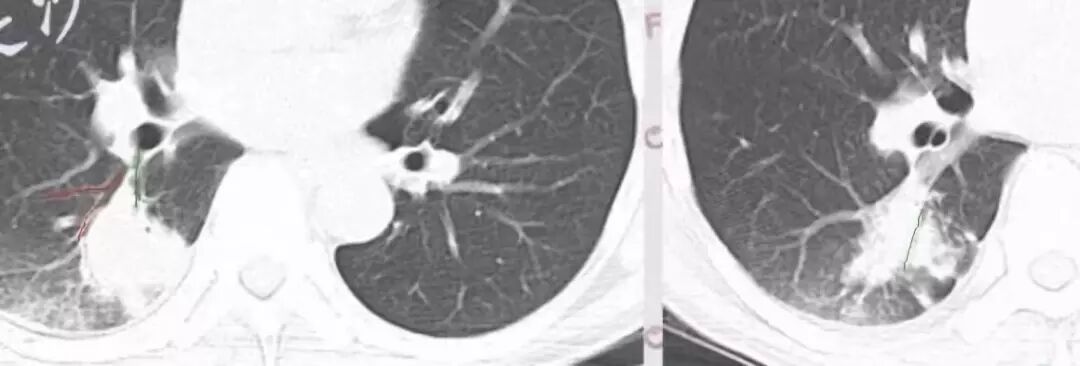

DWI值对鉴别脑脓肿与囊性脑转移瘤有重要意义。包膜期脑脓肿其内容物主要为炎症细胞、微生物及蛋白质,其黏稠度相对较高,水分子弥散受到限制,DWI表现为均匀高信号。转移瘤囊变区主要以浆液性坏死物为主,其黏稠度相对较低,水分子扩散速度相对较快,DWI表现为低信号

脑脓肿和囊性脑转移瘤的鉴别点就是粘液(结合水)浆液(自由水)的鉴别

下图是例举其他病例: